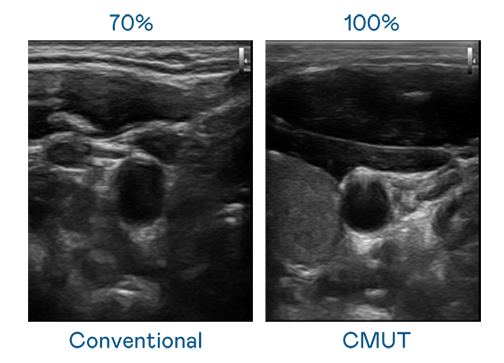

CMUT 技术是一种用电容式微机电元件来产生超音波讯号的技术。与传统 PZT 压电式技术相比,CMUT 频宽增加 30%,更宽频的超音波讯号让影像解析度大幅提升,是实现高影像品质医疗超音波扫描、促进精准医疗发展的关键技术。

超音波影像的解析度高低,首先取决于探头能发出的讯号频宽。PG国际 CMUT 可提供高清晰的超音波讯号,提供高频宽、高灵敏度、影像纹理细节更高的超音波影像,协助医护人员缩短影像判读时间及利用精准的医疗影像进行诊断。